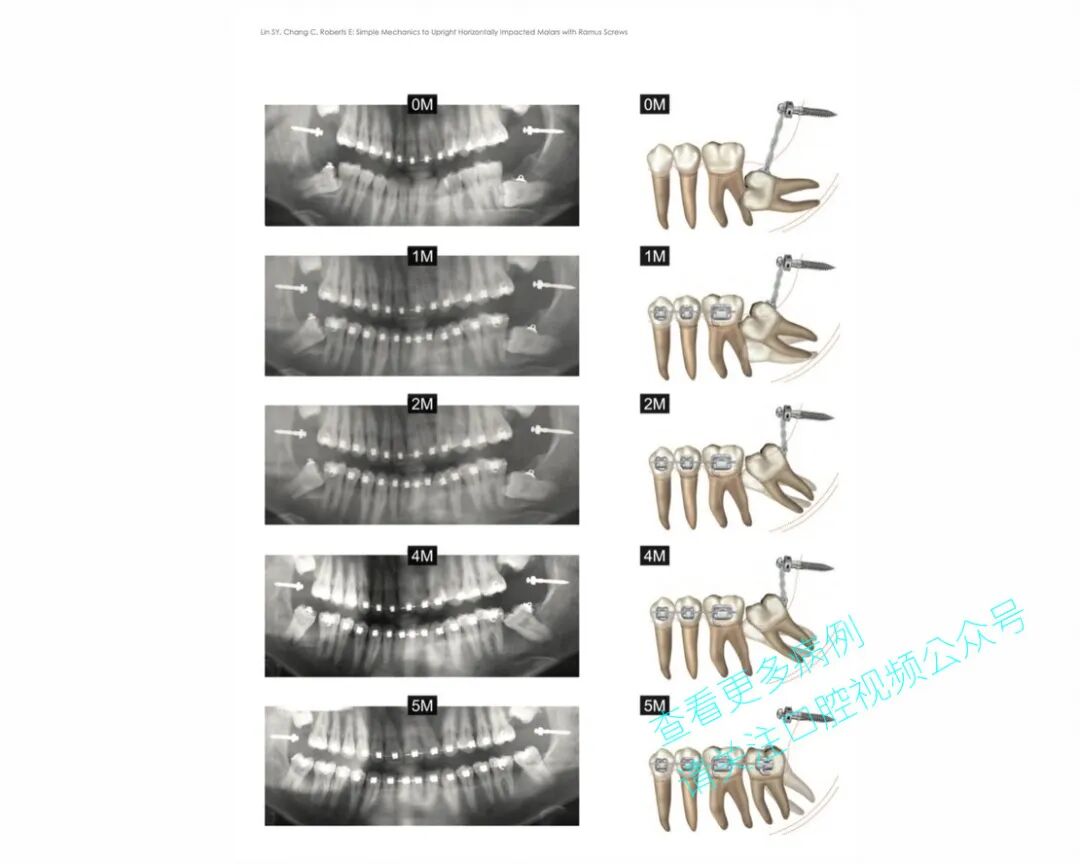

患者为18岁男性,既往接受过正畸治疗。37号牙水平阻生,紧贴36号牙。

手术拔除了38号牙,并在下颌升支植入一枚2×14 mm微型种植体,用于牵引并使37号牙平行移动。

该病例虽复杂,但取得了良好效果,成功避免了在青少年患者中植入种植体。